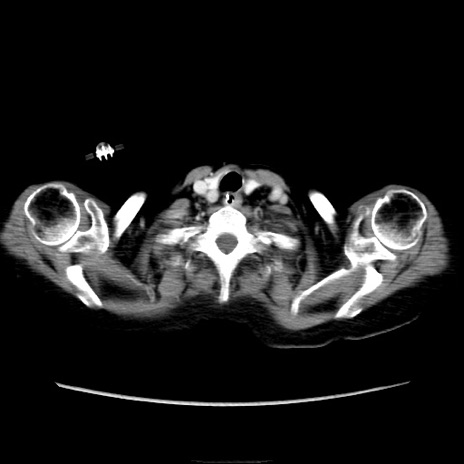

他院CT

横断像